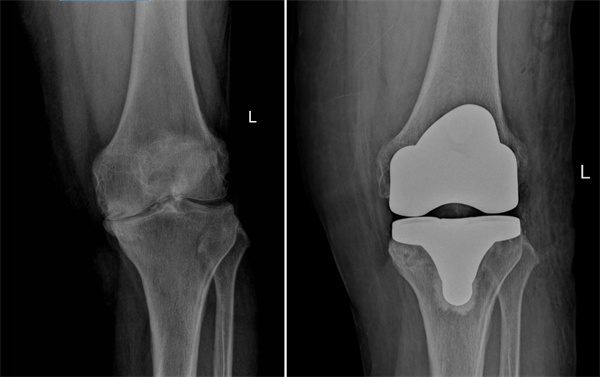

左膝术前术后对比

2022年10月,张阿姨在湖南省第二人民医院骨关节运动医学科诊断为双膝重度骨性关节炎,并接受右膝关节置换手术。出院后主治医生积极微信与患者保持联系,指导康复训练,定期复查,右膝关节功能恢复良好,也不痛了。但是左膝关节问题同样明显,跛行严重,为进一步提高生活质量,解决疼痛问题,2025年9月,张阿姨再次来到湖南省第二人民医院骨关节运动医学科,于近日顺利接受左膝关节置换。术后第一天,即可在助行器辅助下下地行走。目前,张阿姨正在进一步康复中。